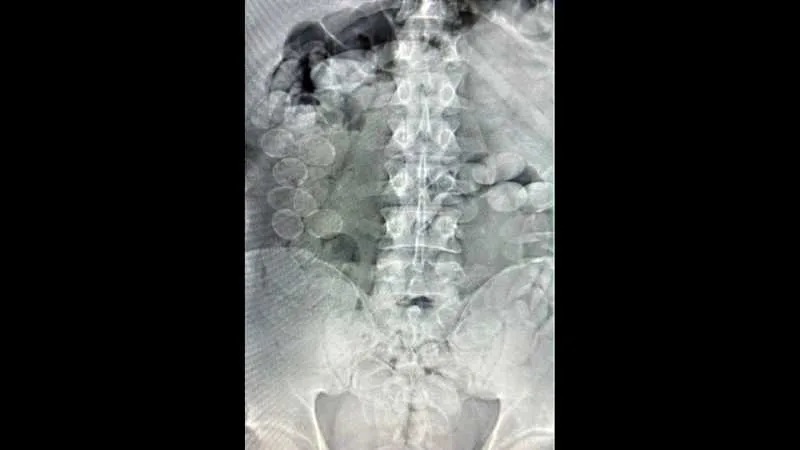

Ante la gravedad de la situación, GNA informó lo sucedido a la Sede Fiscal Descentralizada Rafaela, que ordenó el inmediato traslado e internación de los involucrados al Hospital de Ceres, donde los estudios radiográficos confirmaron la presencia de cuerpos extraños compatibles con cápsulas en sus organismos.

Finalmente, expulsaron un total de 185 cápsulas de cocaína: 93 envoltorios con 1.239 gramos extraídos de Quispe Carmona y 92 envoltorios con 1.212,3 gramos correspondientes a Rocha Risco. El pesaje total, fue de 2.451,3 gramos de cocaína —casi dos kilos y medio— con una pureza promedio del 85,17%. Según expuso la fiscalía al momento de la audiencia de formalización de la investigación, esa cantidad habría permitido obtener más de 20 mil dosis.